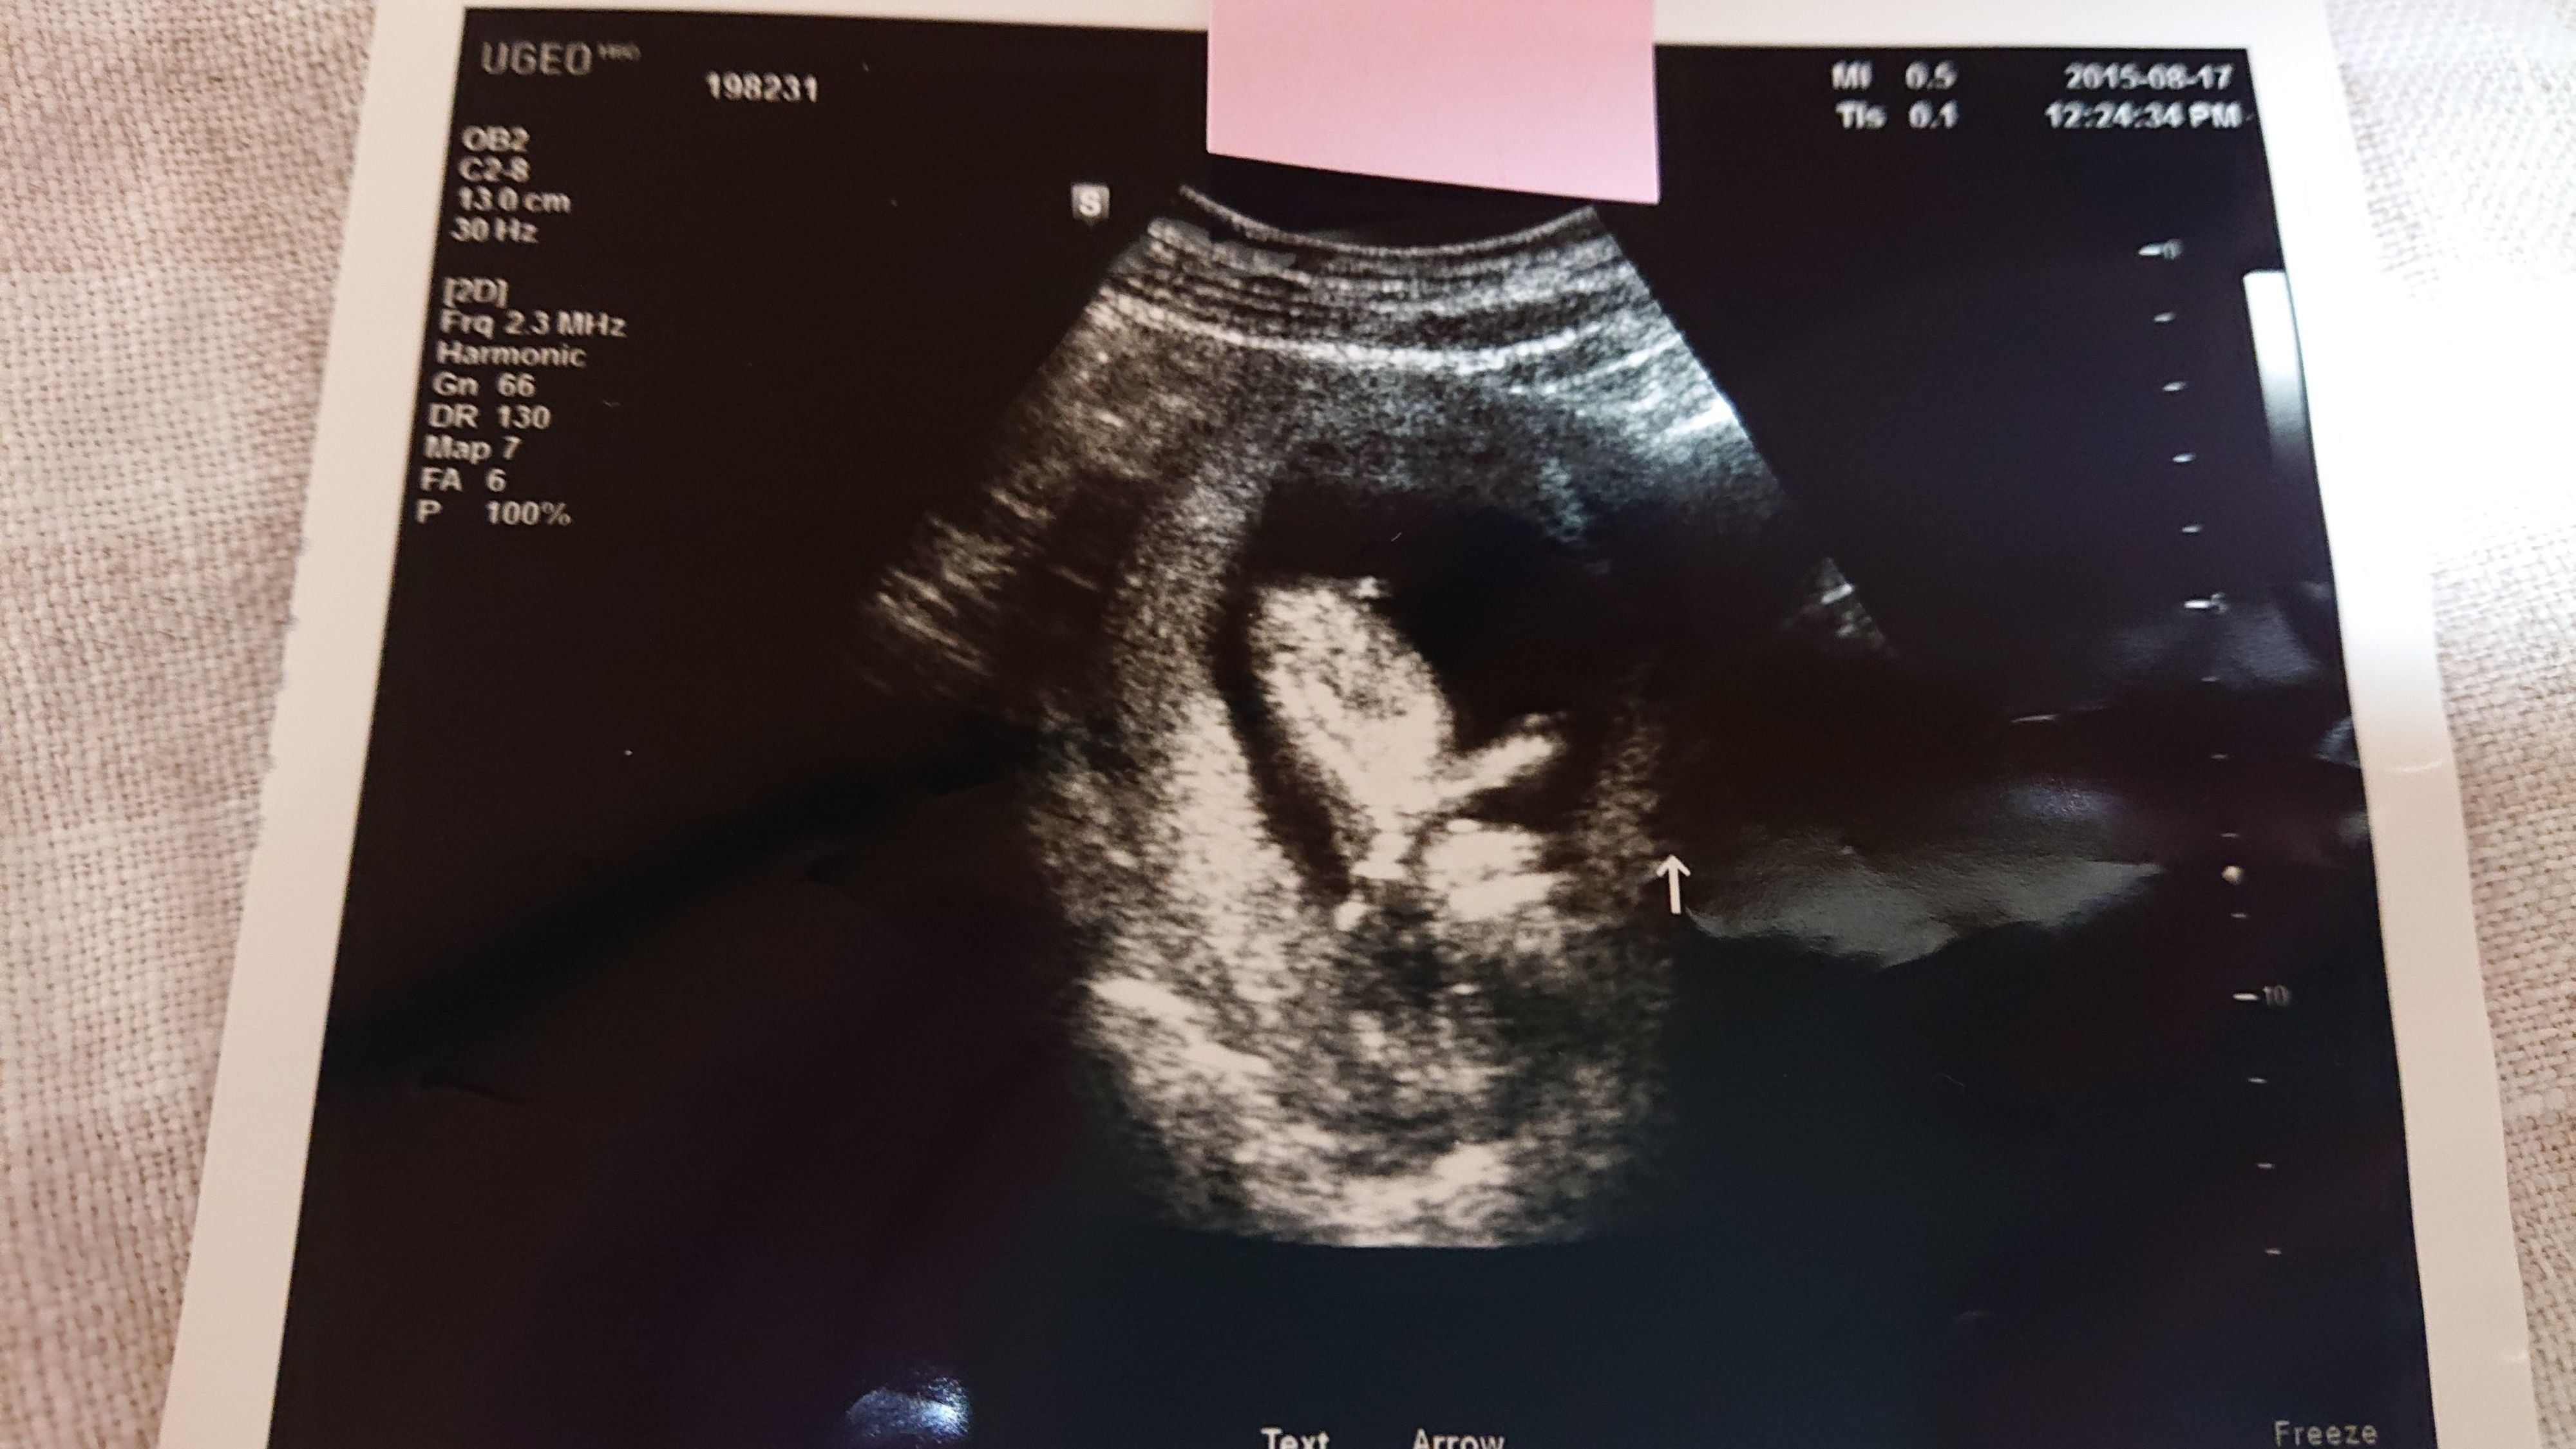

《妊娠9週目のエコー写真》

前回のエコー検査から2週間が経った妊娠9週での健診。この2週間で医師もびっくりするくらい赤ちゃんが大きくなりました。「急に大きくなりすぎて予定日が確定しがたいな~」と告げる医師。3月上旬くらいという話だった予定日が、2月20日ごろに変更となりました。小さな小さな手足もできていて「人っぽくなってきた」と赤ちゃんの存在をより実感した1枚です。矢印の部分が手足です。